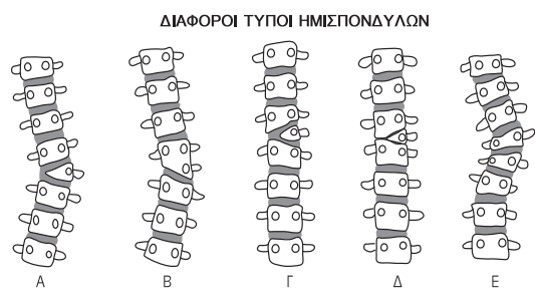

Οι ανωμαλίες σχηματισμού διακρίνονται σε πλήρη ετερόπλευρη (αληθής ημισπόνδυλος) και μερική ετερόπλευρη έλλειψη σχηματισμού (εμπιεσμένος ή τραπεζοειδής σπόνδυλος). Η πιο συνήθης πλήρης ετερόπλευρη διαταραχή σχηματισμού είναι ο συγγενής ημισπόνδυλος (από τα συχνότερα αίτια συγγενούς σκολίωσης).

Υπάρχουν τέσσερις διαφορετικοί τύποι ημισπονδύλων, οι οποίοι καθορίζονται ανάλογα με την παθολογική ανατομική τους και τη σχέση τους με γειτονικούς σπονδύλους.

Αυτοί είναι :

α. Ο διαστηματοποιημένος ημισπόνδυλος με κ.φ. (κατά φύση) μεσοσπονδύλιο δίσκο ύπερθεν και κάτωθι αυτού.

β. Ο ημι-διαστηματοποιημένος ημισπόνδυλος με κ.φ. (κατά φύση)μεσοσπονδύλιο δίσκο είτε ύπερθεν είτε κάτωθι αυτού, αλλά όχι εκατέρωθεν.

γ. Ο μη διαστηματοποιημένος ημισπόνδυλος χωρίς μεσοσπονδύλιο δίσκο και επιφυσιακή πλάκα ύπερθεν και κάτωθι αυτού.

δ. Ο εγκλωβισμένος ημισπόνδυλος, ο οποίος διατηρεί άνω και κάτω επιφυσιακή πλάκα, αλλά όμως συνοδεύεται από σπονδυλικά σώματα ύπερθεν και κάτωθι αυτού, περιορίζοντας έτσι τη σκολιωτική παραμόρφωση.

Εικόνα 13